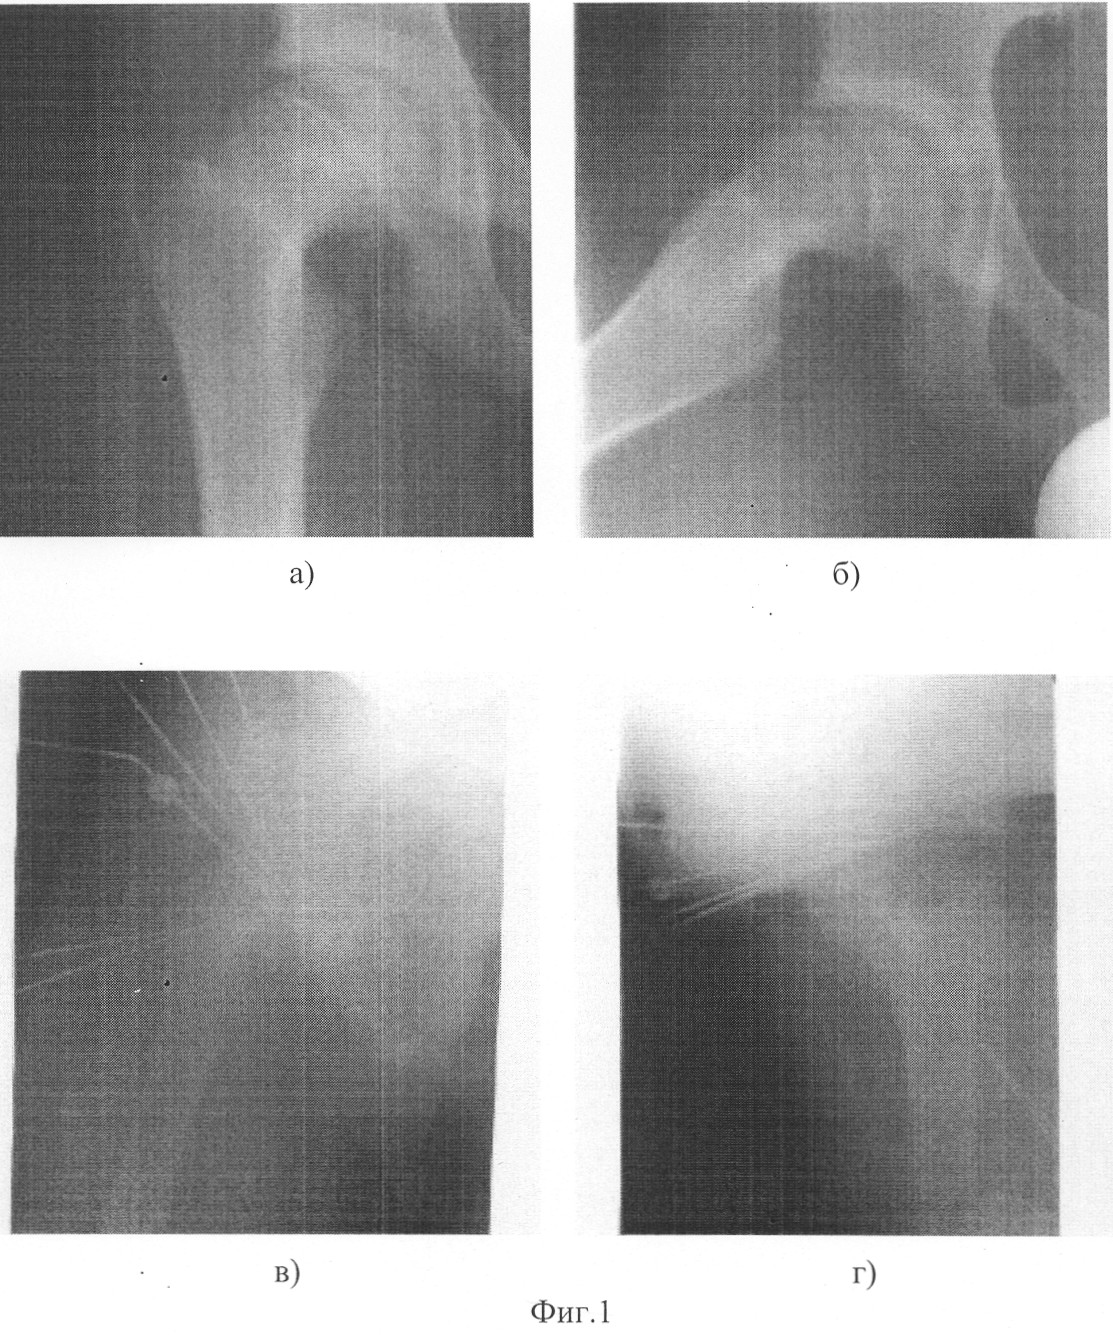

Фоторентгенограммы больного К. произведены на чертеже,

д – остеосинтез бедренной и подвздошной костей аппаратом Илизарова с созданием условий разгрузки в тазобедренном суставе;

е, ж – отдаленный результат.

В ходе операции, согласно предложенному способу, после центрации эпифиза относительно вертлужной впадины путем установки бедра в положение максимальной наружной ротации, полного разгибания и приведения 15 градусов, его фиксировали четырьмя трансацетабулярно введенными спицами. После этого, сгибанием до 60, внутренней ротацией на 70 и отведением на 15 градусов, выполнили репозицию эпифиза и шейки, которые фиксировали введенным по оси шейки пучком спиц. Удалив трансацетабулярно введенные спицы, бедро вывели в положение нормокоррекции и с применением аппарата Илизарова произвели остеосинтез подвздошной и бедренной костей с созданием условий разгрузки в тазобедренном суставе.

В послеоперационном периоде, до полной консолидации фрагментов бедра, в течение 67 дней осуществляли аппаратную фиксацию области тазобедренного сустава с поддержанием в нем условий разгрузки. При выписке больному в течение 3-х месяцев была рекомендована ходьба с костылями при постепенном увеличении нагрузки на оперированную конечность. Осложнений, связанных с проведением закрытой репозиции и аппаратной фиксации, не отмечалось.

На контрольном осмотре через шесть месяцев больной жалоб не предъявляет: ходит не хромая, с полной нагрузкой на ногу без дополнительных средств опоры, ось конечности правильная, движения в тазобедренном и коленном суставах в полном объеме; рентгенологически – полная консолидация эпифиза и шейки в анатомически правильном положении.